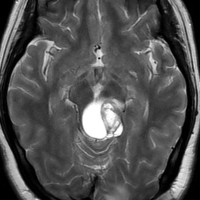

左はT2強調画像,右はFLAIR画像です。中脳視蓋 tectum の中でも上丘が腫瘍化していることが解りますし,松果体は正常の大きさで腫瘍の上に乗っていますから,松果体腫瘍ではないことが解ります。上髄帆にも浸潤しています。